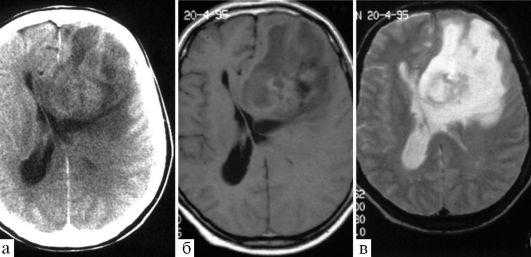

(а) МРТ, Т2-ВИ, аксиальный срез: у юноши с мозжечковой симптоматикой в задней черепной ямке определяется отграниченное гиперинтенсивное на Т2-ВИ объемное образование.

Отсутствие перифокального отека характерно для пилоцитарной астроцитомы. На постконтрастных изображениях определялось контрастирование пристеночного солидного компонента.

(б) МРТ, постконтрастное T1-BИ, аксиальный срез: у ребенка определяется крупное объемное образование, состоящее из кистозного и солидного компонентов.

Обратите внимание на масс-эффект, оказываемый образованием на окружающие структуры. Крупные размеры и гетерогенный характер контрастирования образования могут наводить на мысль о его более высокой степени злокачественности.

При резекции была выявлена пилоцитарная астроцитома (ПА) grade I.